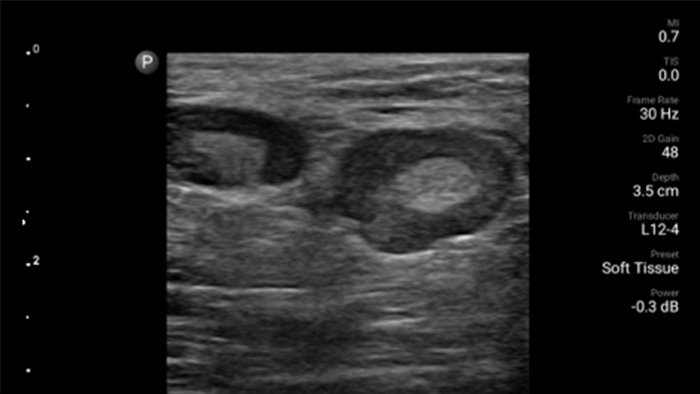

Przenośny system Lumify do stosowania w anestezjologii pomaga wyraźnie uwidocznić granice tkanek, otaczające je nerwy, naczynia oraz powierzchnie powięzi podczas wprowadzania igły.

System Lumify pomaga wyraźnie zwizualizować wprowadzaną igłę, otaczające ją nerwy, naczynia oraz powierzchnie powięzi.